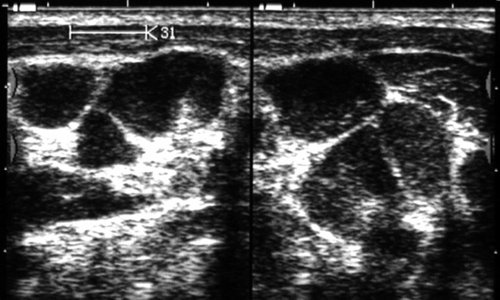

При слюннокаменной болезни, наиболее часто встречающейся в поднижнечелюстных железах, ультразвуковое исследование позволяет выявить конкременты независимо от их расположения (в паренхиме железы, внутрижелезистых протоках, выводном протоке) и степени их минерализации, уточнить наличие сиаладенита - воспаления паренхимы железы, которое может быть самостоятельным или сопутствовать слюннокаменной болезни (рис. 8-11).

Рис. 8. Слюннокаменная болезнь. Обызвествленный конкремент в области перегиба выводного протока (типичное место) левой поднижнечелюстной железы. Сопутствующий сиаладенит.

Рис. 9. Слюннокаменная болезнь. Необызвествленный конкремент в ампулярной части выводного протока поднижнечелюстной железы.

Рис. 10. Слюннокаменная болезнь. Обызвествленные конкременты в паренхиме левой поднижнечелюстной железы. Перифокальный отек паренхимы железы.